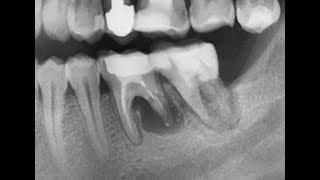

инфильтрационная анестезия первого narkozzz.ruration anesthesia of the first molar

lower jaw block Gow-Gates (анестезия по Гоу-Гейтсу)